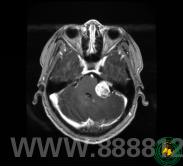

术前影像-左侧桥小脑角区域见肿瘤占位

通过详细的检查,确定了肿瘤位于左侧后颅窝桥小脑角区,是听神经瘤。